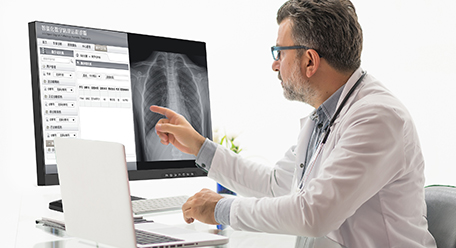

Diagnostic radiology display

Diagnostic radiology display

Application fields: Radiography room/film reading room/ radioautography workstation/imaging equipment.